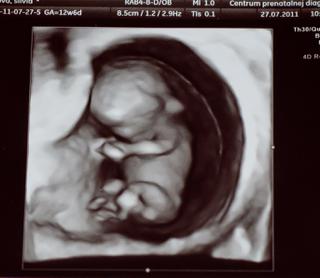

silvia.t to je naozaj super urobena fotecka jaaaj taku ja asi mat nebudem ☹ a kolko si mala nameranu hodnotu NT?

silvia.t nooo ja sa neviem nikde dopatrat k dajakym hodnotam, ktore su v poriadku ☹ teraz neviem ked ty mas hodnotu 0.9mm a ja mam 2.3 ci je to dobre alebo zle ☹

ahojky, taky jsem byla dnes na kontrole, dělal mi screening a NT máme 0,9mm a tuším že do 2,5mm je to ok.mimi se má čile k světu 😉

•NT (nuchal translucence) - šíjové projasnění plodu ve 12. týdnu těhotenství, hodnota víc jak 3 mm svědčí pro možnou genetickou vadu plodu

@lenca.b aj mne tak povedala, ze do 2,5 mm je to ok. ale tvoje mimco je starsie, nie? to zavisi aj dost od velkosti plodu.

funny no to neivem dost sa mi odlisuje termin PM od UTZ terminu ☹ a babo malo 60 mm taaak teda neviem no ale tak ked to je hranica do 2.5 a ja mam 2.3 tak by to snad malo byt ok